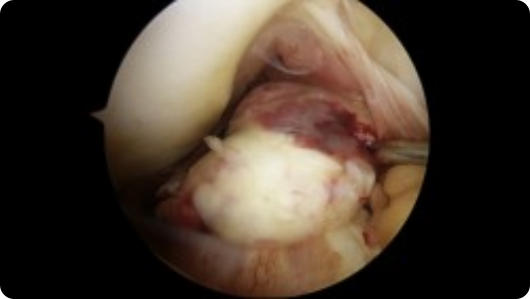

This page contains arthroscopic and radiography images of joint injuries and conditions, and the surgical repairs performed by Dr. Joshua Landau.

Arthroscopic image of a rotator cuff tear Arthroscopic image of a repaired rotator cuff

Rotator Cuff Tear

Rotator Cuff Repair